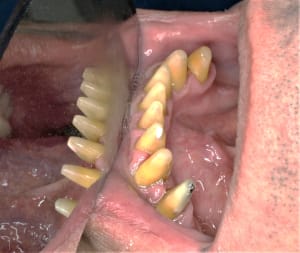

0A49BEBE-5EBF-4385-8CD2-B8EF582DCB11.jpg